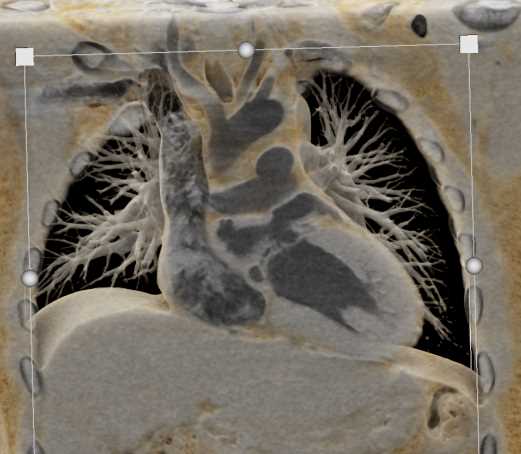

Aortic Valve Repair